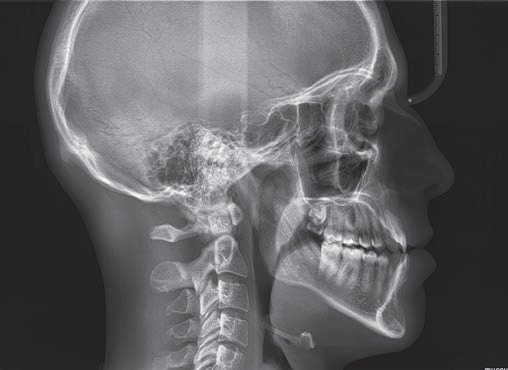

Hyperion X5全景、头颅和X射线体层摄影设备

Hyperion X5不断进化发展,现在头颅及3D拍摄也来到您的面前。这边在整个拍摄过程中快速易用,确保了高分辨率的3D和2D图像、低辐射时间以及实时诊断所需的快速数据处理,改善医患沟通。新的虚拟控制面板简化了拍摄流程,并引入了上颌窦容积检查和正交全景图像的新程序。由于3D传感器模块的自动伺服控制运动,较短的检查时间确保了连续的愉快体验。